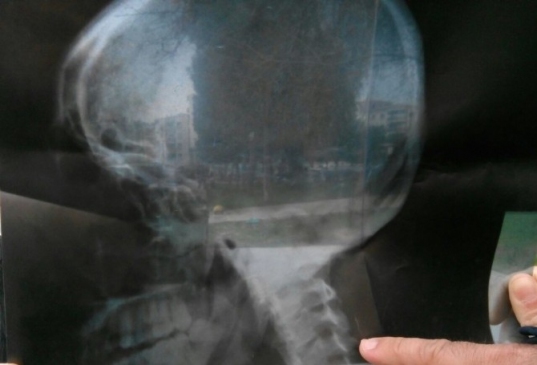

Omurilik ameliyatı sonrasında kafatasında iğne parçacıkları unutulan Salih Aktaş, Türkiye’de doktorların ameliyatını yapmaması üzerine çareyi Almanya’da bulacak.

İzmir’de bir devlet hastanesinde omurilik ameliyatı olan belediye işçisi Salih Aktaş’ın kafatasında iğne parçacıkları unutuldu. Durumu yargıya taşıyan Aktaş’a ikinci şok bilirkişi heyetinden geldi. Olayda kusur bulunmadığı ifade edilen bilirkişi raporunda, iğne parçacıklarının insan vücuduna yararlı olduğu ifade edildi. Doktorlara dava açan Aktaş, önce 8 bin TL kazandı. Ancak, doktorların konuyu Yargıtay’a taşımasıyla Aktaş, 20 bin TL borçlu çıkarıldı ve maaşına haciz konuldu.

İzmir’de, 25 Nisan 2007’de yapılan ameliyatın ardından sağlığı ve psikolojisinin bozulduğunu aktaran Aktaş, iğneleri kendisinde sürekli baş ağrısı oluşturduğu gerekçesiyle aldırmak istedi. Türkiye’de ameliyat olabilmesi için bütün kapıların yüzüne kapandığını öne süren Aktaş, çareyi Almanya’da buldu. Şifa bulmak için gittiği Almanya’da gerekli mercilere başvuran Aktaş, Almanya’dan gelecek olan davetle ‘ameliyat vizesi’ alarak Almanya’ya gidecek.